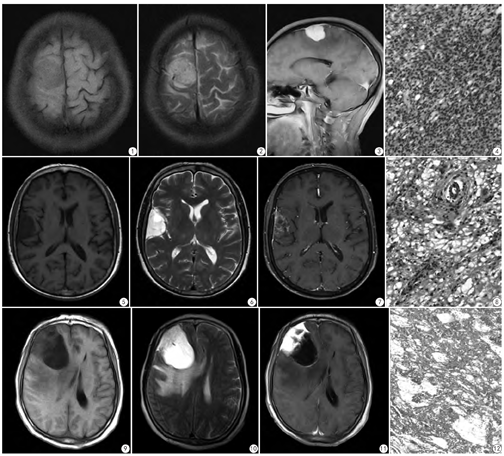

20例肿瘤发生于大脑半球凸面者9例,大脑镰旁7例,上矢状窦旁3例,蝶骨嵴1例。17例肿瘤与相邻硬脑膜呈宽基底改变;3例肿瘤与相邻硬脑膜无宽基底改变。20例肿瘤相邻颅内板骨质增生12例,相邻颅内板骨质无异常改变8例。10例肿瘤周围水肿显著,8例瘤周水肿轻微,2例瘤周无水肿。20例肿瘤无分叶15例,分叶5例。20例中1型9例(40.9%),2型5例(22.7%) ,3型6例(27.2%) ;9例1型均为实性肿块,T1WI呈低信号,T2WI呈高信号,MRI增强扫描肿瘤显著均匀强化(图1,图2,图3,图4);5例2型均似囊性肿块,T1WI呈显著低信号,T2WI呈显著高信号,MRI增强扫描肿瘤呈网格、片絮、辐射状轻度强化,其中2例肿瘤边缘可见囊状无强化区(图5,图6,图7,图8);6例3型均为囊实性肿块,实性部分T1WI呈稍低信号,T2WI呈稍高信号,囊性部分T1WI呈低信号,T2WI呈高信号,增强扫描肿瘤实性部分显著强化,囊性部分无强化,囊壁轻度强化(图9,图10,图11,图12)。

20例肿瘤组织切面呈灰白色,9例瘤体质中,11例瘤体质软。1型以实性细胞为主,显微镜下瘤细胞呈实性片状为主,大小一致,排列整齐,核圆形,染色均匀,其间可见瘤细胞空泡融合成微囊结构,间质血管增生(图4)。2型以微囊型为主,显微镜下瘤细胞大小一致,核圆形,染色均匀,形态温和,细胞间呈空泡状,多个空泡融合成微囊,个别囊腔内见嗜酸性黏液滴,间质血管增生(图8)。3型以囊实性为主,镜下见瘤细胞间空泡融合成微囊,部分囊腔扩张,囊内可见黏液样物质。微囊之间瘤细胞增生,呈实片状,大小一致,核圆形,染色均匀,形态温和,间质血管增生(图12)。16例免疫组化上皮膜抗原EMA及波形蛋白VIM均(+),GFAP、CK、S-100蛋白均(-)。ki67<1%。

既往文献报道,微囊型脑膜瘤的CT表现可呈等、低、稍高密度[7],目前尚未见国内外文献对本病钙化的报道。钙化发生的原因主要是肿瘤组织中碱性磷酸酶含量增高,发生钙化多见于良性脑膜瘤血供不太丰富或病程缓慢者[8]。本组病例MRI信号符合多数文献报道,即长T1、长T2信号特征[2,9]。其形成与肿瘤细胞排列疏松、微囊内嗜酸黏液聚集导致瘤体质地柔软,瘤体内含水丰富相关[2]。本组瘤周水肿的高发生率亦与文献报道相符[9]。既往研究认为水肿指数可作为WHO Ⅰ级的罕见类型,广泛的瘤周水肿表明存在WHO Ⅰ级的罕见类型[10],近年研究认为瘤周水肿主要为瘤周脑组织静脉回流受阻所致[11]。结合本组病例,与既往文献对比[2, 9,12],笔者认为微囊型脑膜瘤强化方式主要包括显著均匀强化和不均匀强化,其中不均匀强化包括辐射状条絮样强化及片絮样轻度强化。尽管显著均匀强化所占比例较高,但与其他类型脑膜瘤相比无显著差异,而不均匀强化所包含辐射状条絮样强化及片絮样轻度强化与其他类型脑膜瘤相比具有一定特征,笔者发现,本组病例的这一强化特征在其他的文献报道中亦得到印证[13],只是这一强化特征发生的比例较少。在最近大宗病例的研究中[7],将微囊型脑膜瘤的MRI分为3型,其中1型指肿瘤显著均匀强化,本组9例属1型;2型指瘤体内网格或片絮状、辐射状轻度强化,肿瘤边缘强化,本组5例属2型;3型指肿瘤大部囊变,其位于宽基底部实性部分显著强化,囊壁轻度环形强化,本组6例属3型。除1型以外,2、3型均可发生囊变,其中3型囊变程度及范围最显著。需要指出的是,微囊是显微镜下特征,尽管呈长T1、长T2信号,在未发生囊变的病例中,其内部会强化。微囊型脑膜瘤并非囊性脑膜瘤,但部分病例可发展成囊性脑膜瘤。本组病例囊变主要发生在肿瘤周边,根据囊性脑膜瘤分类[14],属Nauta Ⅱ型。